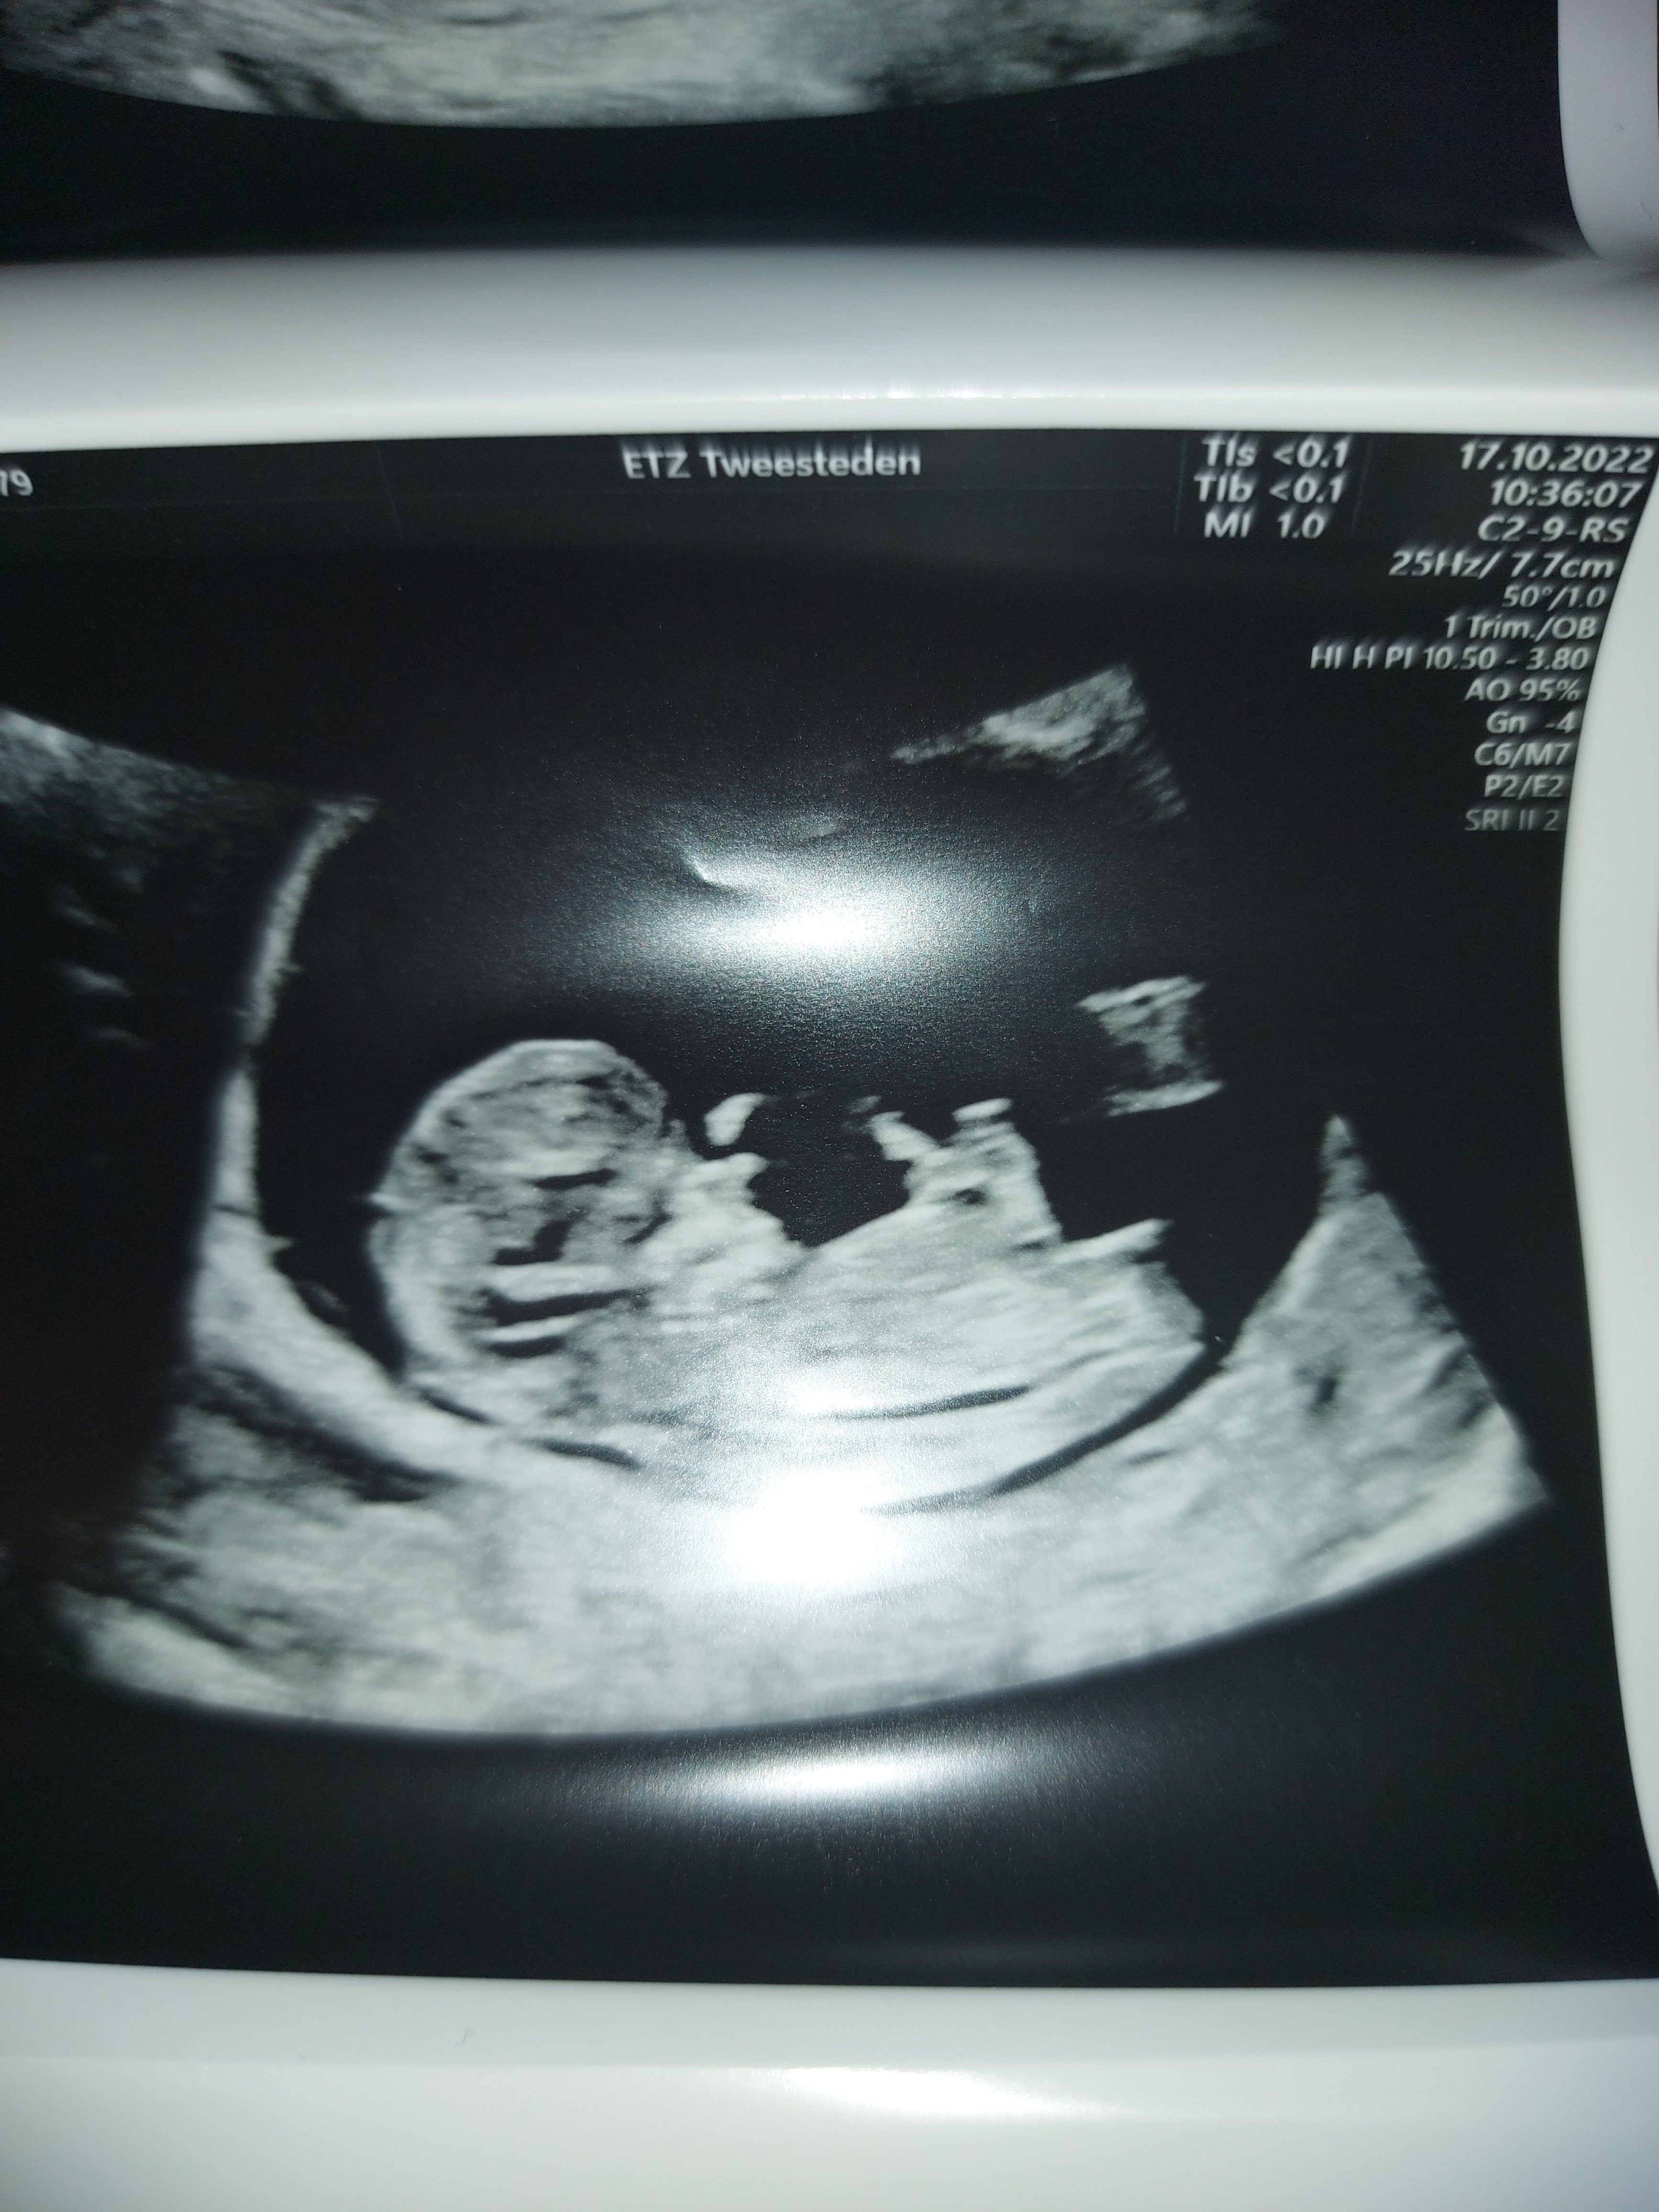

Bebeğimin cinsiyetini ogrenebilirmiyim? 11hafta 1 gunluk

Selamlar bir tanem, bizimkisi ilgili teoriye göre tahmindir bilginiz olsun. Görüntü sola biraz daha yakın olduğu için erkek diyebiliriz. Ama doğrusunu Allah bilir. Sevgiler sunuyorum.

Bu arada Nub teorisine göre baktım resmi siz atınca bunda da kız görünüyor 🙂 Elinizde başka foto var ise ekleyebilir misiniz ?